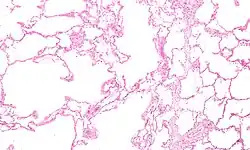

| Micrograph of an emphysematous lung; emphysema is a respiratory disease, strongly associated with smoking. H&E stain. | |